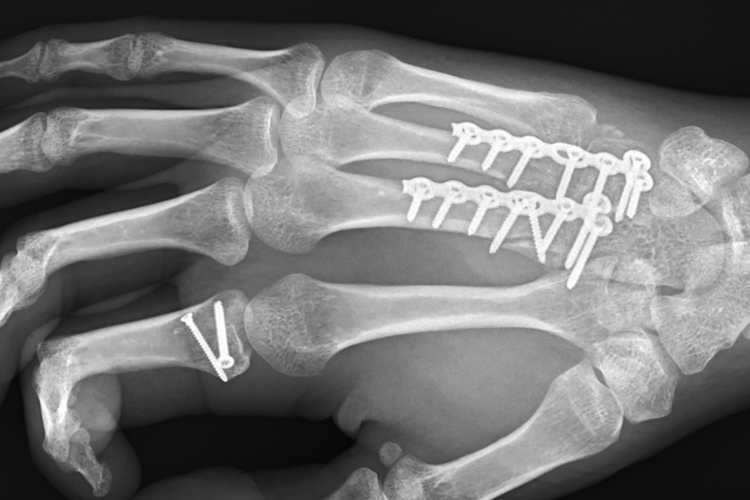

Dominic Schmitter hätte Mitte April bei der Superbike-WM in Assen mit Wildcard fahren sollen. Doch bei einem Test in Cartagena zog er sich am 19. März in der rechten Hand drei Trümmerbrüche, einen Gelenkbruch sowie drei gerissene Sehnen zu. Inzwischen hat sich der Rheintaler von den Verletzungen gut erholt, die Beweglichkeit der Gashand wird täglich besser. "Die Knochenbrüche sind verheilt, die Durchblutung sei gut, sagte mir mein Arzt beim letzten Besuch", erzählte Schmitter SPEEDWEEK.com. "Sofern mir die Dorna das Okay gibt, sollte meinem Wildcard-Start in Misano nichts im Weg stehen."

"Mein Ziel sind immer Siege", unterstreicht der demnächst 25-Jährige. "Mühe macht mir wahrscheinlich die Beweglichkeit im Handgelenk. Das ist wegen der Platten, die bleiben bis Ende Jahr drin. Im Idealfall behindern sie mich nicht. Mein Arzt sagte mir, dass alles so gut verheilt sei, dass ich mir keine Sorgen machen brauche. Ich könnte sogar auf die Hand stürzen. So eine Heilung hätte er noch nie erlebt, meinte er und sprach von einem Wunder. Und der Doc steht kurz vor der Pension."